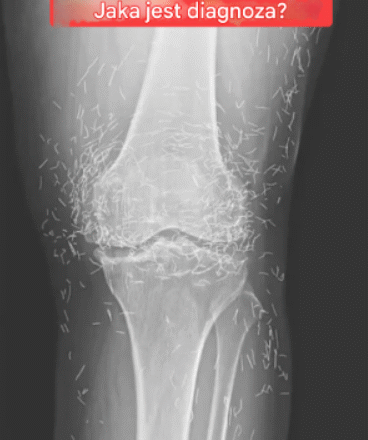

Lekarze badając zdjęcie rentgenowskie kolan starszej kobiety cierpiącej na silny ból stawów, odkryli prawdziwą żyłę złota: setki maleńkich złotych igieł do akupunktury pozostawionych w jej tkance.

W raporcie czytamy, że podczas zabiegu akupunktury u kobiety celowo pozostawiono igły, prawdopodobnie wykonane ze złota, w celu dalszej stymulacji.

Mogą one również utrudniać lekarzowi interpretację zdjęcia rentgenowskiego. „Igły mogą zasłaniać część anatomii” – powiedział Guermazi.